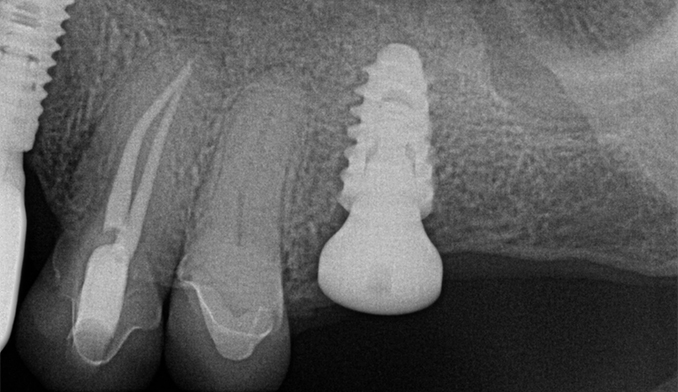

Molar Extraction, Bone Grafting, and Implant Placement

The patient’s lower right molar was severely damaged and could not be saved. After removing the tooth, we performed bone grafting to preserve the bone structure, ensuring a strong foundation for future treatment. Four months later, after proper healing, a dental implant was placed to restore function and maintain jaw health.